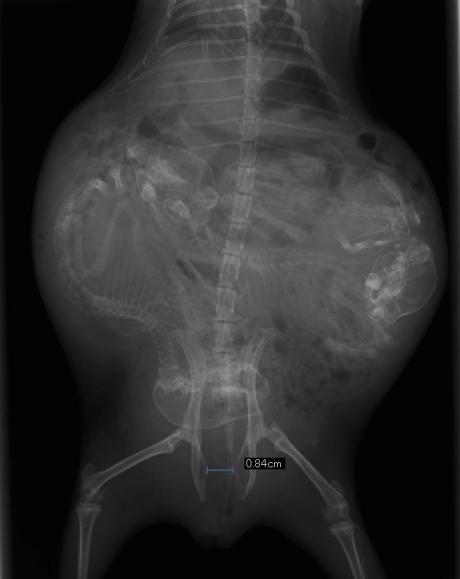

6月17日のレントゲンにてお腹の中に3頭の仔を確認しました。

恥骨結合がどのくらい開いているか確認し、21日~24日ごろには生まれる予想でした。

↑仔の頭蓋骨や背骨が確認できます。恥骨結合の開きは0.84cmでした。